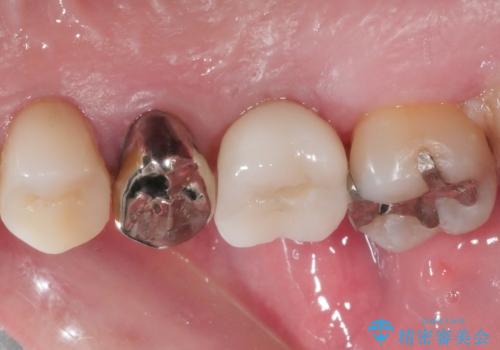

- 奥歯で噛んだ時の違和感を主訴に来院された患者様です。

歯根の先端の病変が大きく割れてしまっていた為、抜歯の必要がありました。